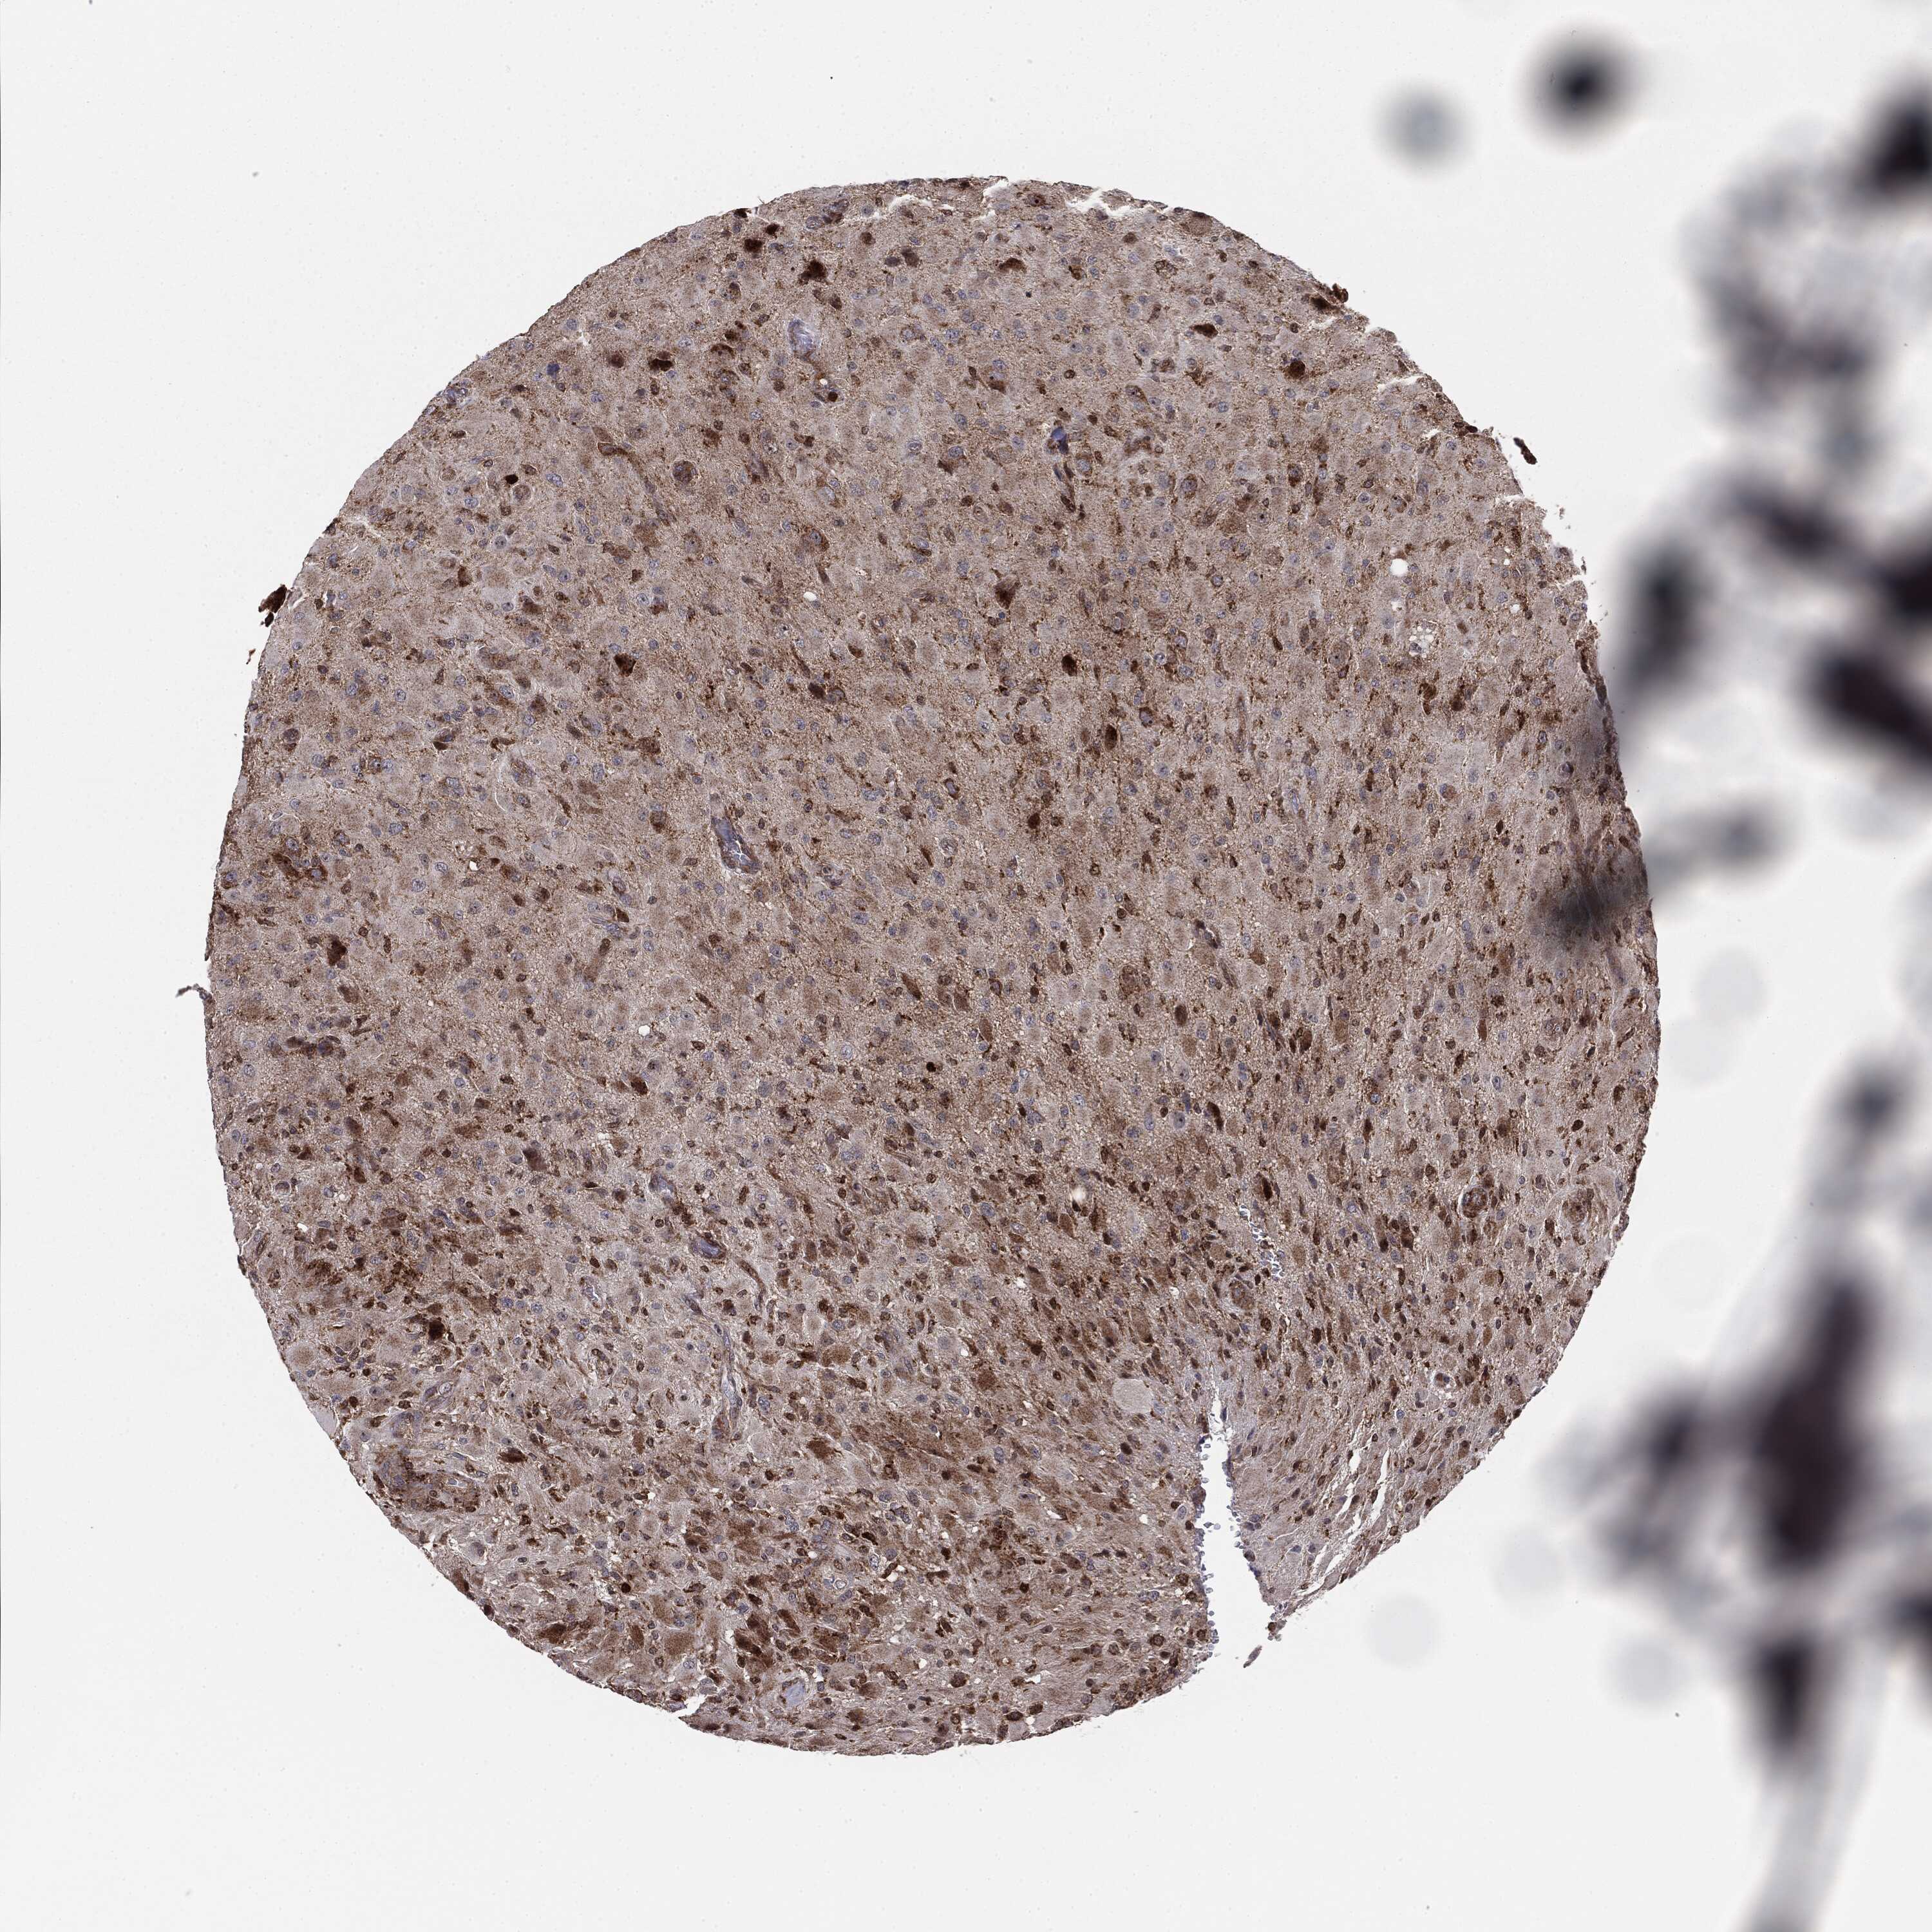

GLIOMA - Protein expressioni

A mouse-over function shows sample information and annotation data. Click on an image to view it in a full screen mode. Samples can be filtered based on level of antibody staining by selecting one or several of the following categories: high, medium, low and not detected. The assay and annotation is described here.

Note that samples used for immunohistochemistry by the Human Protein Atlas do not correspond to samples in the TCGA dataset.

Antibody stainingi

Antibody staining in the annotated cell types in the current human tissue is reported as not detected, low, medium, or high, based on conventional immunohistochemistry profiling in selected tissues. This score is based on the combination of the staining intensity and fraction of stained cells.

Each image is clickable and will lead to virtual microscopy that enables deeper exploration of all samples and also displays staining intensity scores, fraction scores and subcellular localization as well as patient and tissue information for each sample.

Antibody HPA031335

Antibody CAB004076

Antibody CAB080153

Antibody CAB080157

Glioma, malignant, Low grade

Glioma, malignant, High grade

Glioma, malignant, NOS